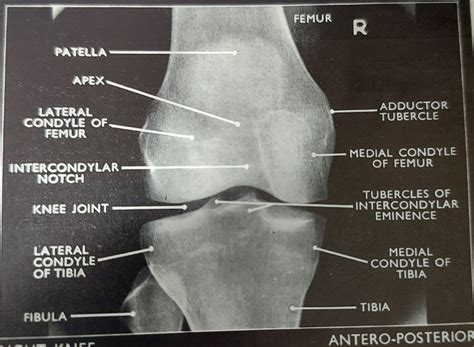

The distal end of the femur is characterized by two tumid condyles - the median and sidelong condyles - which articulate with the tibia to organize the knee joint. The Adductor Tubercle Femur is positioned just superior to the median epicondyle. While it may seem as a elusive protrusion, its role is pivotal for the mapping of the thigh musculature.

In the battlefield of orthopedical medicine, the Adductor Tubercle Femur serves as a vital "anatomical landmark". Surgeons utilize this feature during assorted procedures, specially those regard total stifle arthroplasty (TKA) or corrective osteotomies. Because the tubercle is palpable and relatively consistent in its positioning, it helps surgeon accurately shape the joint line and the axis of the genu.

When critique lateral stifle radiographs, the Adductor Tubercle Femur can ofttimes be identified as a minor jut at the most superior aspect of the medial femoral condyle. Its ocular clarity is important for identifying weather such as pearl spurs (osteophytes) or name the right placement for ironware in femoral break repairs.